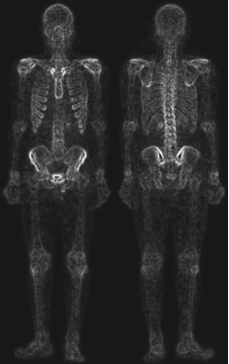

다른 방법은 어떤 방법이 있을 까요? 그 방법은 영상 그래디언트의 스무딩된 버전의 마스크를 사용하는 것입니다. 이러한 과정을 가능한 이유는 미분의 특성에 기인합니다. 라플라시안 필터는 애초에 2차 미분 연산입니다. 따라서 세세한 디테일 개선에는 좋은 결과를 얻을 수 있습니다. 하지만 노이즈가 많은 입력 영상을 받으면 출력 영상 역시 노이즈가 많게 됩니다. 하지만 로버츠나 소벨 연산과 같은 1차 미분 연산자는 라플라시안 필터에 비해서 노이즈나 미세한 디테일에 적은 반응을 보이고, 노이즈나 미세한 디테일을 얻는다고 해도 스무딩을 통해 제거 가능합니다. 따라서, 그래디언트 기반의 필터링을 통해서 엣지를 추출한 뒤 혹시나 남아있는 노이즈를 제거하기 위해 스무딩을 적용하는 것을 샤프닝된 영상의 입장에서는 골격의 마스크로 볼 수 있기 때문에 두 영상을 곱한 결과를 사용하는 것이 합리적입니다. 이를 위해서 위의 사진과 같이 입력 영상에 소벨 연산을 적용하게 됩니다.

다음으로 기울기 영상에 스무딩을 적용하여 약간의 노이즈를 제거해줍니다. 그러면 이를 마스크로 취급하고 샤프닝된 영상과 곱을 취해줍니다.

그 결과 영상 내의 강한 엣지들이 더 많이 남아있으며 노이즈는 라플라시안만 활용한 것에 비해서 더 줄어든것을 관찰할 수 있습니다. 이제 강한 엣지 영상을 샤프닝하는 데 사용해주면 됩니다.